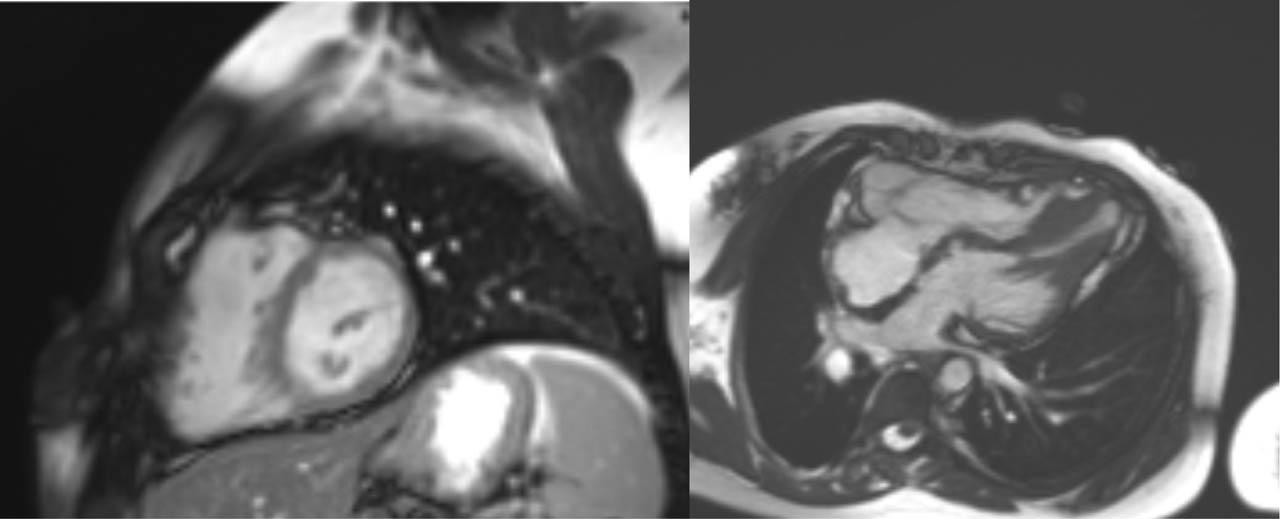

Figure 6

Cine end-diastolic images: Left: short axis at the level of the papillary muscles. Right: four chamber view. Apical left ventricular hypertrophy with a normal sized right ventricle can be observed.